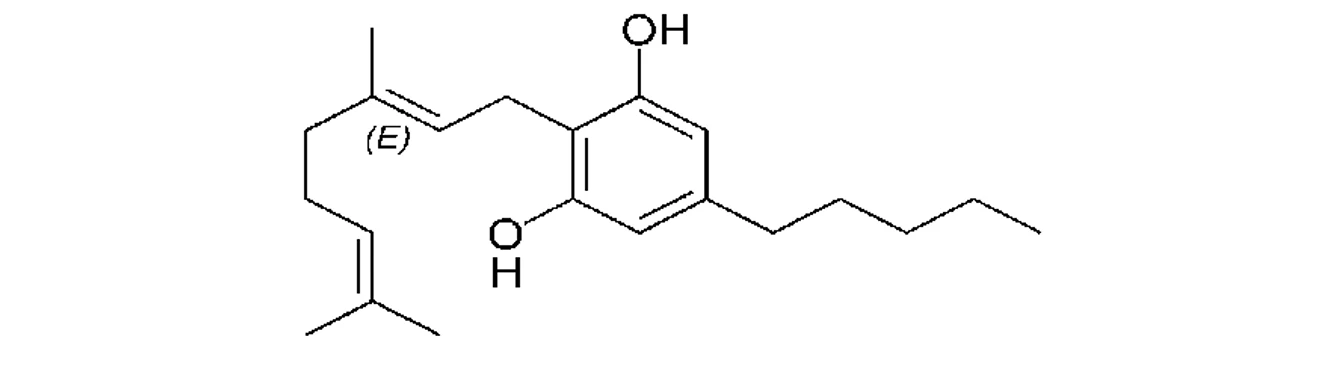

PČR: Kanabigerol (CBG) – první izolovaný kanabinoid z pryskyřice marihuany, má antibakteriální účinek (10)

PČR: Kanabigerol (CBG) – první izolovaný kanabinoid z pryskyřice marihuany, má antibakteriální účinek (10)